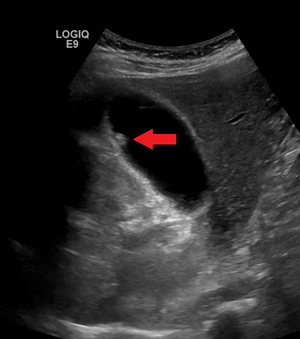

Adenomyomatosis describes a diseased state of the gallbladder in which the gallbladder wall is excessively thick, due to proliferation of subsurface cellular layer. It is characterized by deep folds into the muscularis propria. Ultrasonography may reveal the thickened gallbladder wall with intramural diverticulae, called Rokitansky-Aschoff sinuses.[3]

Diagnosis is typically by ultrasound or CT imaging.